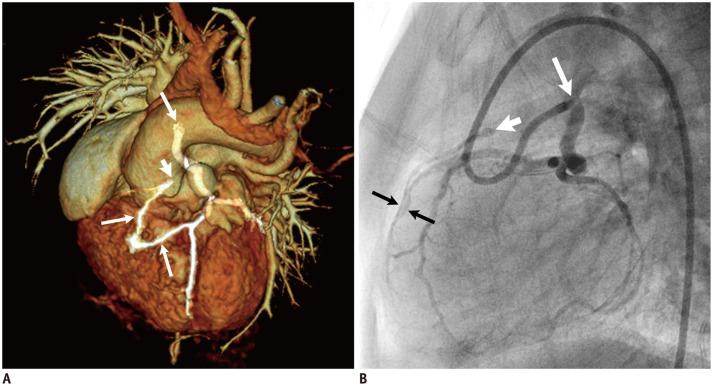

Coronary artery problems in children usually have a significant impact on both short-term and long-term outcomes. Early and accurate diagnosis, therefore, is crucial but technically challenging due to the small size of the coronary artery, high heart rates, and limited cooperation of children. Coronary artery visibility on CT and MRI in children is considerably improved with recent technical advancements. Consequently, CT and MRI are increasingly used for evaluating various congenital and acquired coronary artery abnormalities in children, such as coronary artery anomalies, aberrant coronary artery anatomy specific to congenital heart disease, Kawasaki disease, Williams syndrome, and cardiac allograft vasculopathy.